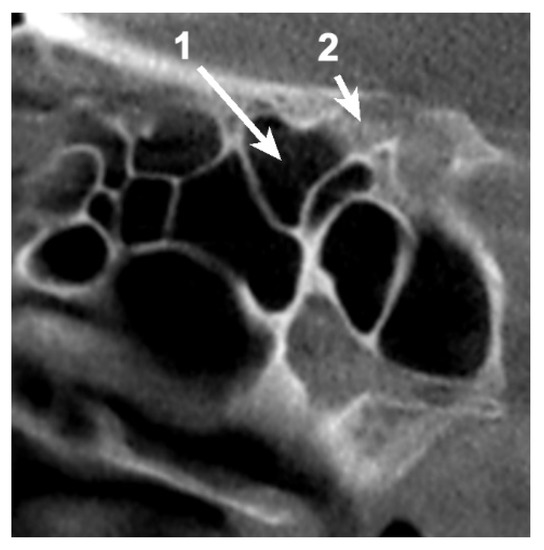

Simultaneous pneumatization of both LSW roots was noted in 31 cases (38.75%) and 43 sides (26.87%) (Table 2; Figure 3). This kind of extensive pneumatization was more frequent in the female group (22 cases, 71%).

Figure 2. Coronal, bilateral three-dimensional volume rendering of the anterior clinoid process (ACP) and sphenoid sinus, posterior view. 1. Pneumatized ACP; 2. Pneumatized optic strut; 3. Pneumatized anterior root; 4. Sphenoid sinus.